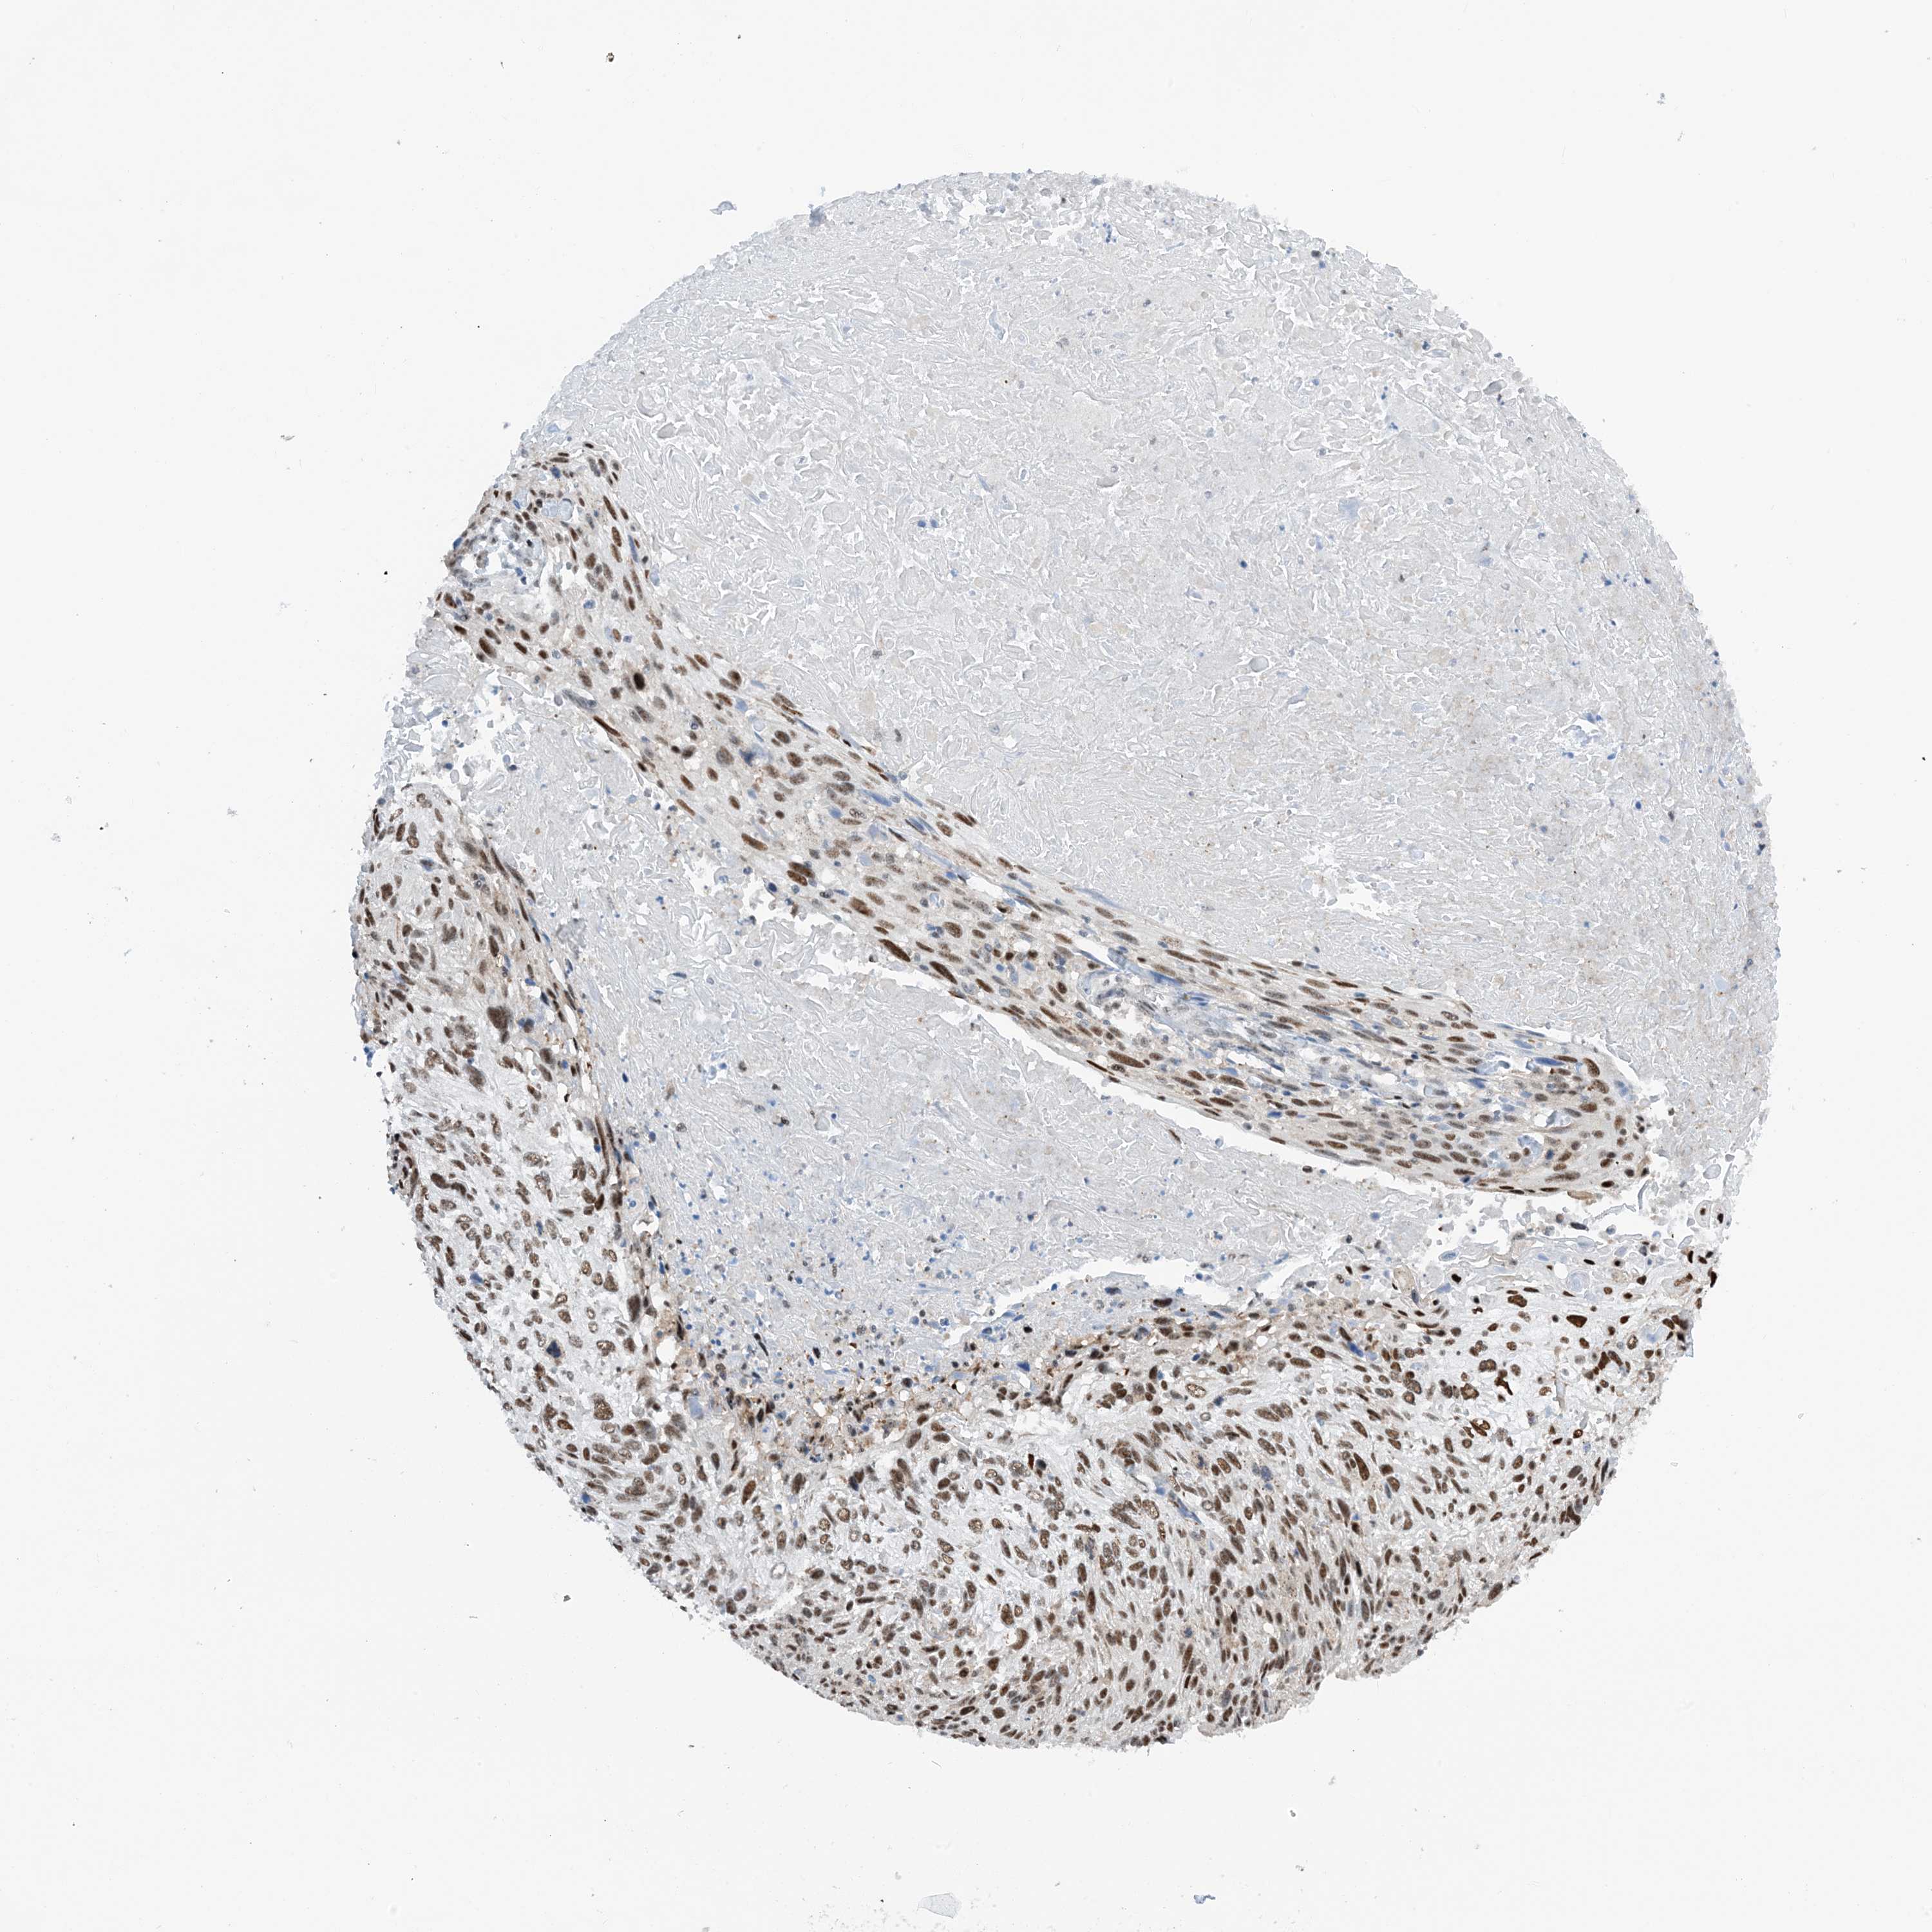

CERVICAL CANCER - Protein expressioni

A mouse-over function shows sample information and annotation data. Click on an image to view it in a full screen mode. Samples can be filtered based on level of antibody staining by selecting one or several of the following categories: high, medium, low and not detected. The assay and annotation is described here.

Note that samples used for immunohistochemistry by the Human Protein Atlas do not correspond to samples in the TCGA dataset.

Antibody stainingi

Antibody staining in the annotated cell types in the current human tissue is reported as not detected, low, medium, or high, based on conventional immunohistochemistry profiling in selected tissues. This score is based on the combination of the staining intensity and fraction of stained cells.

Each image is clickable and will lead to virtual microscopy that enables deeper exploration of all samples and also displays staining intensity scores, fraction scores and subcellular localization as well as patient and tissue information for each sample.

Antibody HPA034701

Antibody HPA034702

Staining

High

Medium

Low

Not detected

Intensity

Strong

Moderate

Weak

Negative

Quantity

>75%

75%-25%

<25%

None

Location

Nuclear

Cytoplasmic/membranous

Cytoplasmic/membranous,nuclear

Squamous cell carcinoma, NOS

Adenocarcinoma, NOS